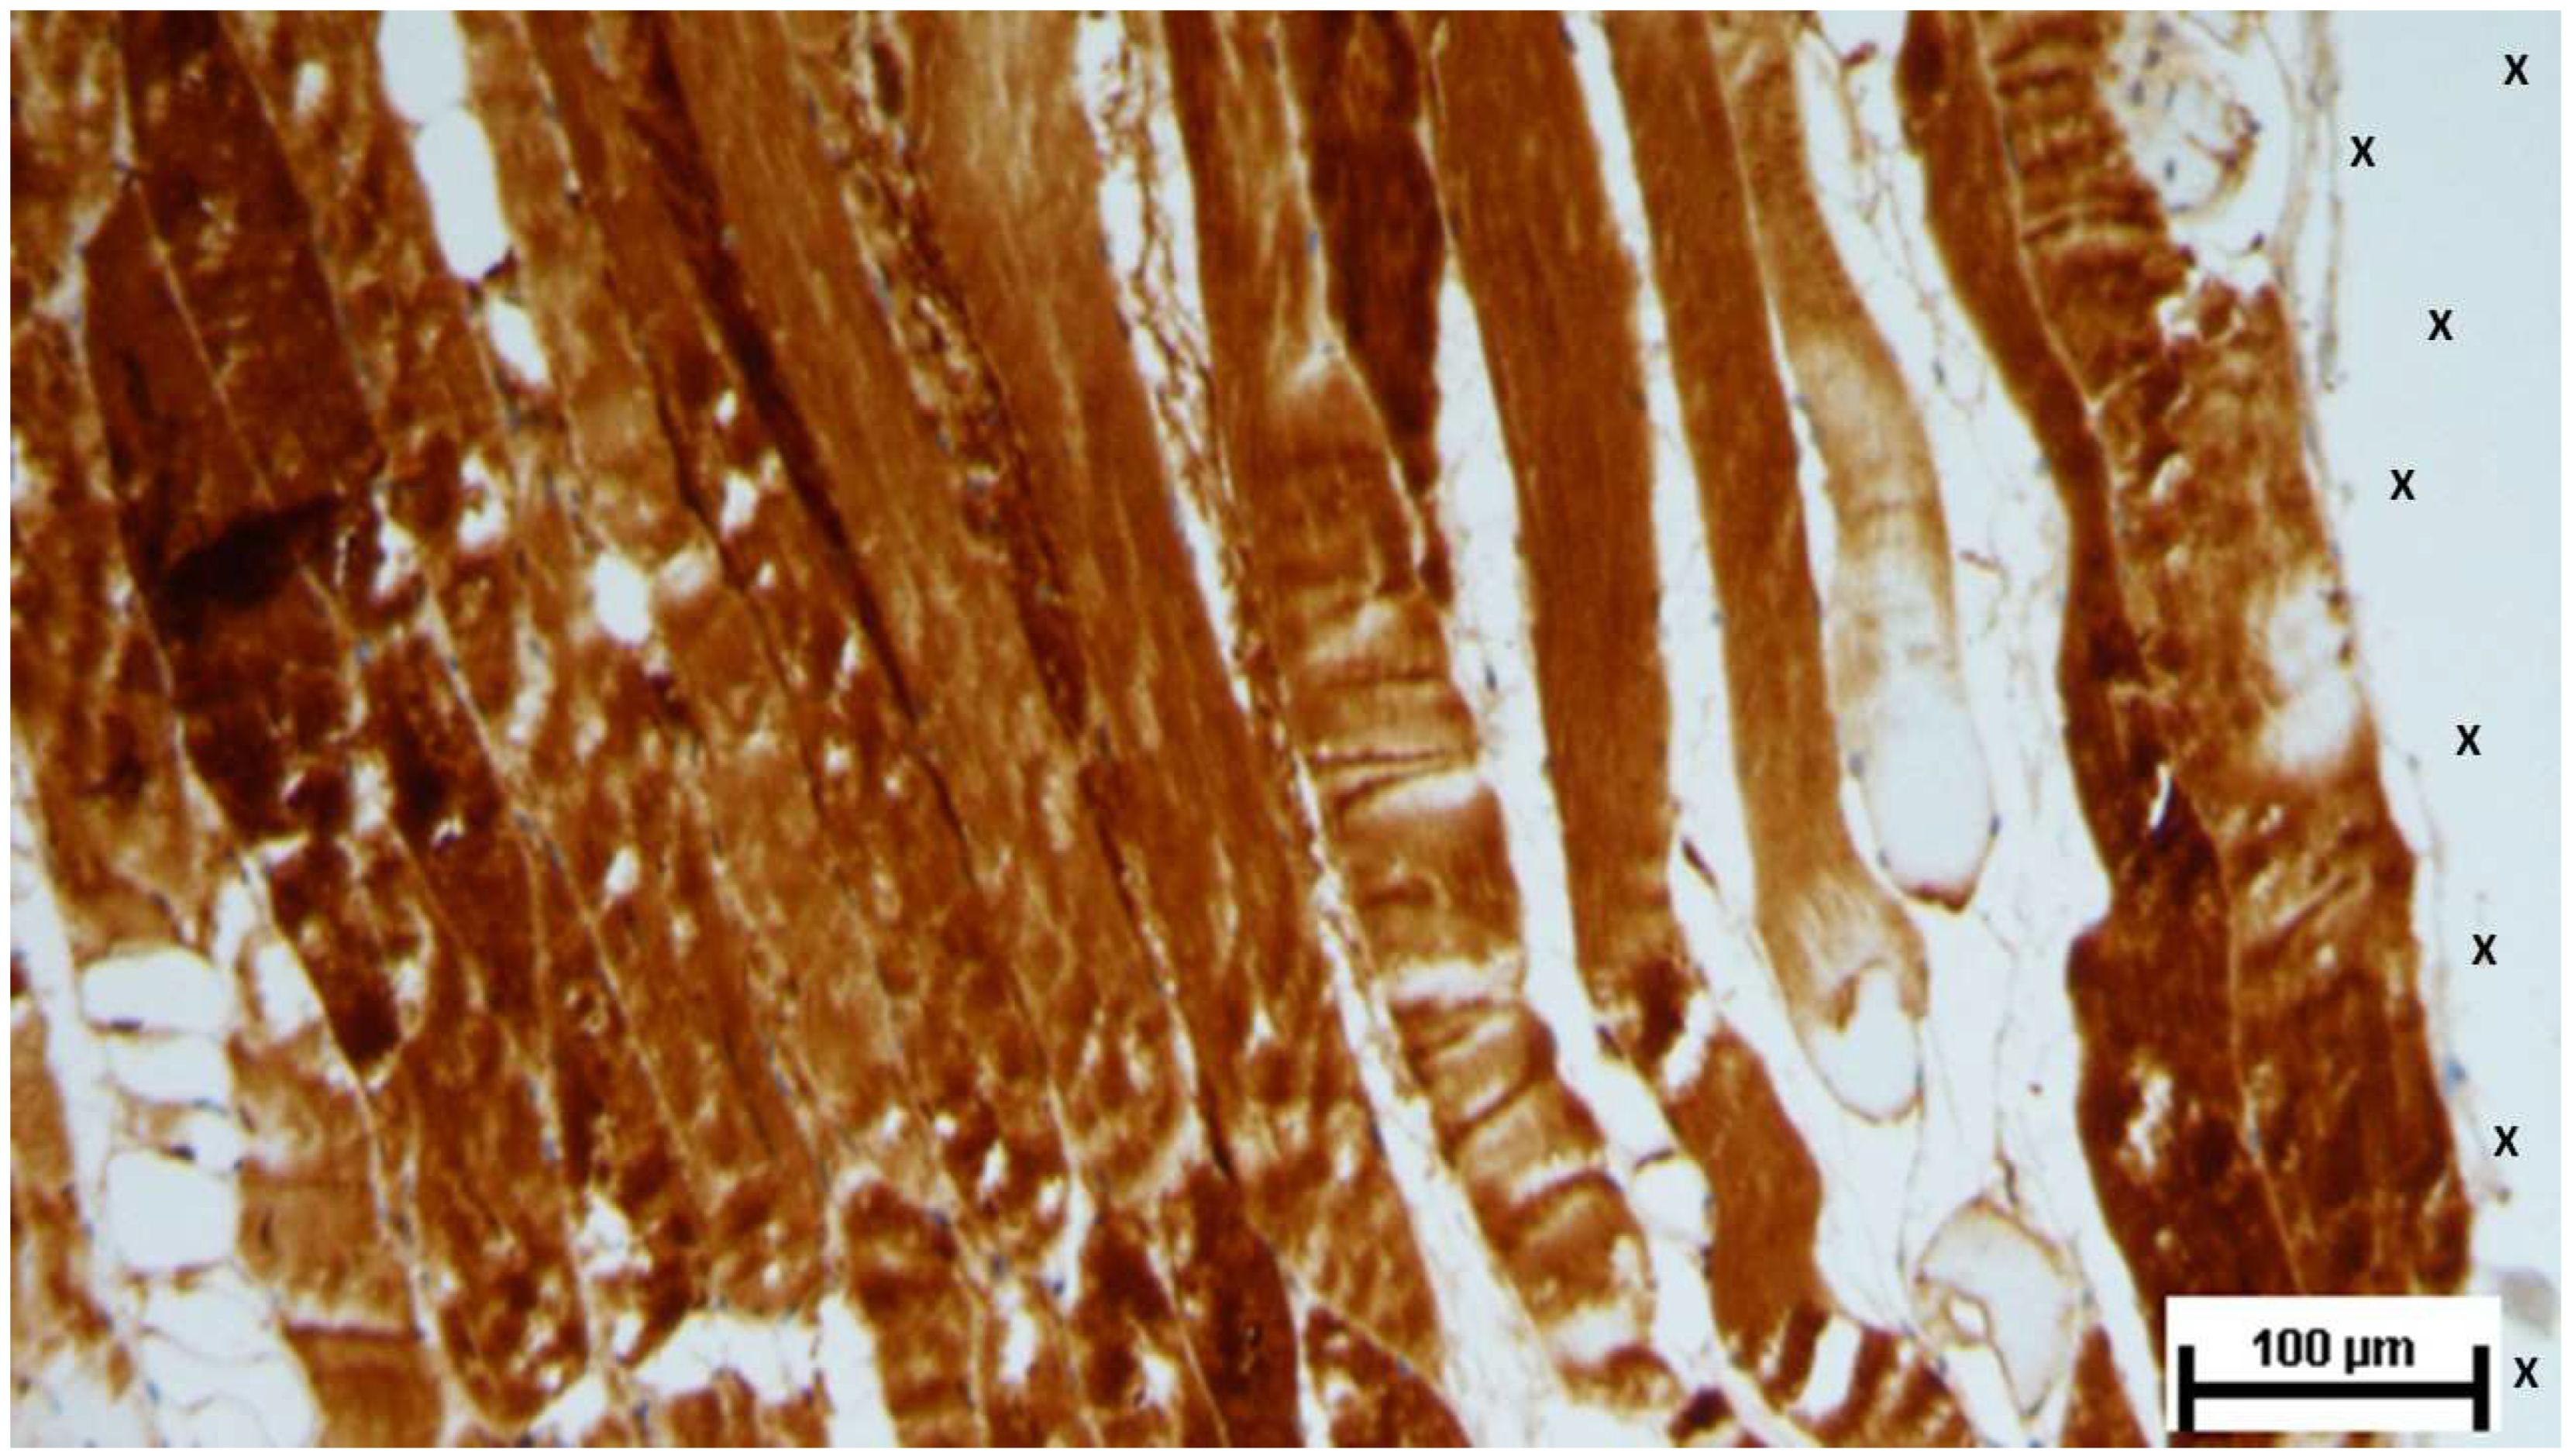

Numerous mature nerve structures were detected adjacent to the scaffold, signifying advanced nerve growth. These nerves, which developed within the S&S device, displayed substantial increases in both myelin and axon formation, resembling typical human nerve structures in terms of their key components (Figure 26).

Figure 26. Biopsy sample removed 7 months post-implantation (Long term - LT). Elongated nerve elements (brown staining) in advanced development are present near the 3D scaffold (X). NSE 100X.